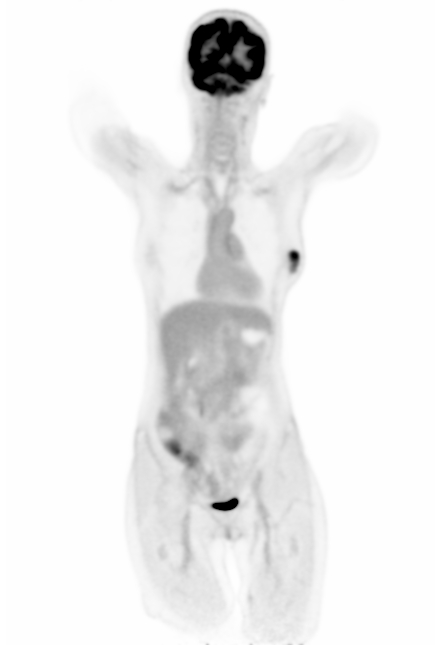

Figure 7 shows three clinical \acFDG dataset examples. The \acDLSE-corrected images are visually very similar to the \acSSS-corrected images. Examining the profile lines in the first row, which displays a breast lesion in a female patient, reveals similar patterns to those observed in the simulated images in Figure 4, with lower activity in the region between the lungs using \acSSS compared to \acDLSE. However, the activities within the lesion are very similar for both \acDLSE and \acSSS.

In the second row dataset, \acDLSE provides better contrast on the nodules than \acSSS, showing similar activity levels between the nodules but with a higher activity peak.

The last dataset shows kidney structures in a large morphology patient (98 kg). The \acSSS-corrected image exhibits an overall higher activity than the \acDLSE-corrected image. After manual segmentation of the kidneys and automatic segmentation of its structures using the FLAB algorithm [37], the contrast is found to be slightly higher in the \acDLSE corrected \acPET images. The contrast is 2.3 with \acDLSE correction, compared to 2.2 with \acSSS correction and 1.8 in the uncorrected image.

| No correction | DLSE | SSS | Profiles |

The study conducted on clinical \acFDG acquisitions demonstrated consistent results for \acDLSE, producing visually comparable outcomes to \acSSS-corrected images (Figure 7). The method appeared to be robust against significant variations in patient morphology, with weights ranging from 52 to 98 kg. In two of the three cases, \acDLSE-corrected images exhibited slightly higher activity levels, while the \acSSS method showed higher activity in the large morphology patient. This discrepancy may be attributed to inaccuracies in the tail-fitting algorithm used to estimate the scaling factor for multiple scatters, as the tails could potentially be too small for larger morphology patients. In all three examples, the lesion contrasts were found to be greater than those obtained with the \acSSS-based scatter correction.